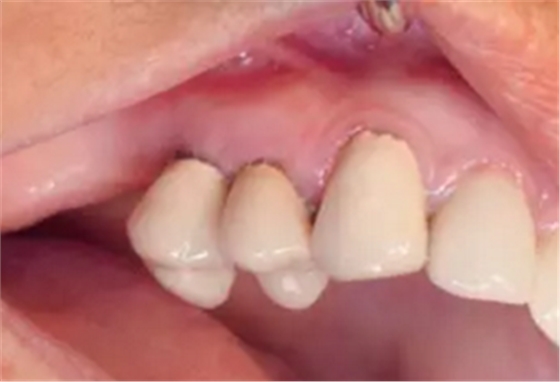

圖21

圖22